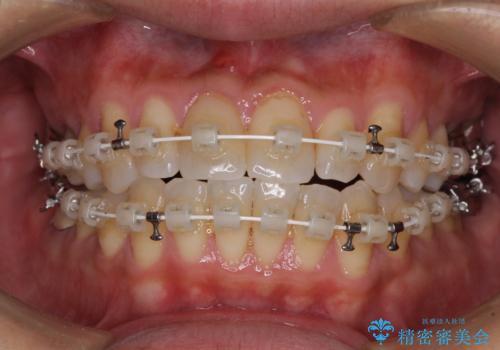

- 審美装置

- 1年2ヶ月

- 10-30回

前歯のクロスバイトは、改善の途中で歯髄壊死を起こすリスクが高くなるため、マウスピース矯正よりもワイヤー矯正をお勧めしております。

この患者様もクロスバイトはあっという間に改善され、1年強で速やかに治療を終えることができました。